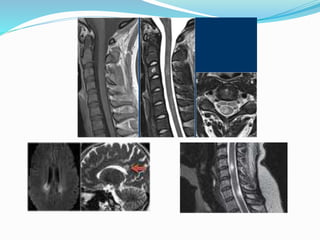

MRI in PPMS

A paucity of focal lesions

Less Gd- enhancing lesion

Fewer new lesions over time

The smaller lesions may be more destructive

More diffuse signal abnormalities

More lesions in spinal cord than brain

Enhancement may be present particularly early on the disease

T2 lesion load correlate with the evolution of disability

T1 lesions and cord ones do not correlate with disability in PPMS.

MRI measures to quantify changes in NABT: Magnetization Transfer Ratio

imaging (MTR), 1H (MRS),and diffusion MRI